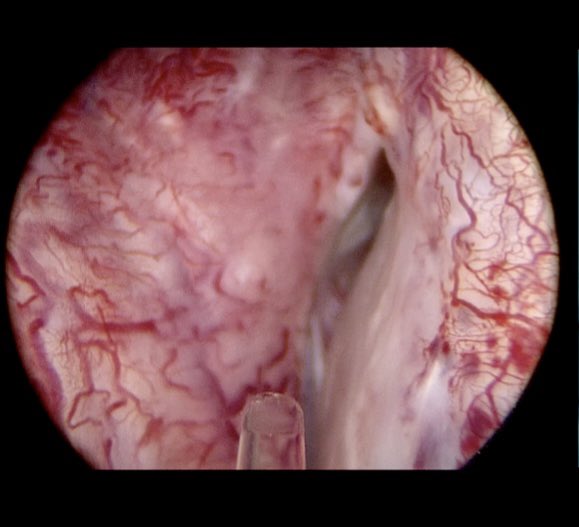

@drtevaho

Tev Aho

3 years

Tomorrow’s MoLEP case at #TNT2022 1145hr is a gentleman with severe urinary symptoms and intermittent total urinary retention which failed to improve after both #prostatearteryembolisation and #rezum. These pictures show a rezum prostatic cavity and blue PAE microspheres